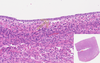

5

Q

Name of the THREE Details:__________?_____________?_______?

A

Lumen – Endometrium – Thinner Endometrium

6

Q

Name of the Detail:______?

A

Myometrium